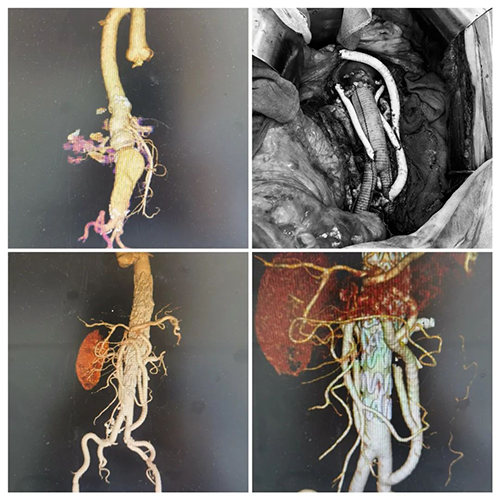

在新疆工作的患者王伯(化名)被诊断患有胸腹主动脉瘤,瘤直径约7.7cm,相当于一个苹果大小。他既往有高血压、冠心病病史,9年前接受了心脏瓣膜修复术,入院两天前于乌鲁木齐某三甲医院检查确诊,由于动脉瘤浸及内脏动脉区,手术难度高、风险大,对手术技术及设备要求很高,患者及家属多方打听,经过深思熟虑,不远千里从新疆辗转至甘肃省中心医院接受治疗。

王伯住院后经过精准的术前评估,双肾动脉自动脉瘤腔发出后严重扭曲且左肾动脉直径4.5mm,单充介入支架修复后预期疗效欠佳,医生与王伯及家属沟通后,建议行杂交手术。这需要切开腹部进行手术,手术创伤大、时间较长,手术中血栓容易脱落发生远端栓塞等严重并发症,围术期风险也较高,除了腹主动脉瘤破裂,王伯还伴有冠心病、高血压等诸多疾病,身体状况较差,这些大大增加了手术难度。

甘肃省中心医院麻醉手术二部有西北地区首家“双C+飞龙+滑轨CT”于一体的复合手术室,精良的手术设备为手术的成功奠定了基础。医务部组建了强大的多学科专家诊疗团队,制订了详细而周全的手术方案,术前进行了充分的评估和准备。鉴于王伯病情危重且紧急,手术团队决定采用腹主动脉瘤切除+人工血管置换术+腹腔干动脉人工血管重建+肠系膜上动脉人工血管重建+双肾动脉人工血管重建+胸腹主动脉瘤腔内支架修复术。

打开王伯腹腔,一个直径约10x7.7cm的巨大动脉瘤映入眼帘,厚厚的血肿覆于周围,一系列挑战才刚刚开始,由于瘤体太大,很容易造成误伤,血管游离难度极大,切除瘤体,植入人工血管,缝合破损的血管同样并非易事。在血管中找到合适的血管走位、对接,缝得滴水不漏,这很考验医生的基本功。进针的角度不对,或者用的针粗细、软硬不合适,血管就会碎裂。而且手术时间太长,病人的机体功能也受不了,因此,要争分夺秒!

手术中一切都有条不紊地进行,人工血管依次与近端腹主动脉、肾动脉、双侧髂总动脉做吻合,并重建肠系膜下动脉,密切监测心率、血压等一系列生命体征,精准、快速用药、输液、补液,对每一个细节都精益求精,及时调整治疗方案,医护人员们密切配合,终于,16:14分,手术顺利完成!

在精心照料下王伯顺利康复,复查CTA检查,手术效果满意恢复情况良好,同时还积极开展心理疏导,让患者和家属感受到了温暖与关爱。